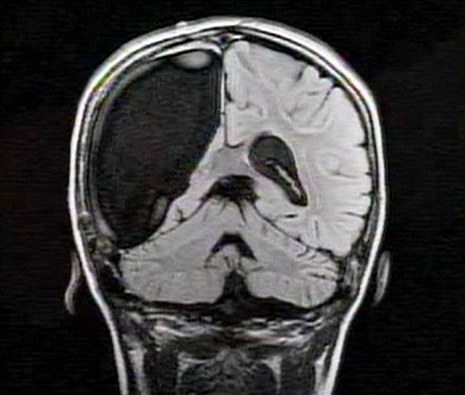

英國9歲女孩切掉半邊大腦 奇跡康復想跳芭蕾(圖)

中新網3月26日電 據英國媒體26日報道,一名9歲的英國女孩在經歷了右腦切除手術后奇跡康復,令醫生和家人無比震驚。

報道稱,現年9歲的卡梅倫•莫特在手術中切除了她整個右半邊的大腦,而在經歷如此重大的手術后能迅速康復,莫特的奇跡也讓醫生和她的家人驚嘆不已。年幼的莫特也沒有因為病癥而放棄對夢想的追求。

卡梅倫莫特在3歲那年患上一種被稱作大腦功能紊亂“拉斯穆森”綜合癥,這種病癥誘發患者的無序暴力行為和嚴重的癲癇。醫生建議,治療這種病癥只能通過嘗試消除引發此癥狀的大腦組織。而手術讓莫特失去了幾乎整個半邊的大腦。

據悉,莫特在手術后已經可以跑動和玩耍,她在術后的第四周離開了醫院。醫生表示,雖然右半邊大腦的切除可能會給莫特帶來半身不遂的風險,但孩子剩余的大腦仍具有很強的重組和布線能力。